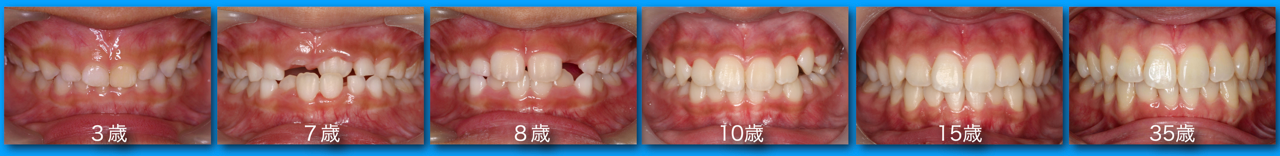

● 咬合育成

子どもたちを虫歯のないきれいな歯並びに誘導していくことが咬合育成で、歯並びが悪くなってから治療する矯正歯科治療とは異なる治療の仕方です。開業時から来院していたこどもたちをどうしたらきれいな歯並びにできるのかを研究してきました。いまではその成果が上がるようになり多くの子どもたちが健康できれいな歯並びをもつ大人になって来院するようになっています。この取り組みは歯科界でも評価され全国の歯科大学や歯科医師会からその分野の講演を依頼されるようになり書籍も出版されて当時はベストセラーになりました。いまでは咬合育成は全国の歯科医院で行われるようになっていますが須貝歯科医院の得意分野になっています。いつもポカンと口を開けて口で呼吸をしていたりするなど、きれいな歯並びになることを妨げる癖もありますがそれらを早く見つけて正しい機能を身に付けさせることも大切です。顎が小さくて歯が並びきらずにガチャガチャの歯並びになってしまうのが日本で一番多い歯列不正です。小さい頃から顎の成長を促す装置をつけて改善することを得意にしています。患者さんによっては矯正専門医に紹介しなければならないケースもあります。その時は地元の信頼できる矯正専門医をご紹介しています。

上の前歯は下の前歯より前にないといけませんが、前歯の生え替わりの時に逆に生えてきましまうことが多くあります。そのままではきれいな歯並びにはなりません。この時が治療のタイミングで、簡単な矯正装置で改善できその後きれいな永久歯列になっていきます。

また乳歯から永久歯への生え替わりを注意してみていくことで多くの歯列不正は予防できます。できるだけ少ない介入できれいな歯並びになることを目指しておりその経験も豊富です。「定期健診に通っていたらいつの間にか虫歯のないきれいな歯並びになった」と思ってもらうことを目標にしています。

定期健診を継続し、虫歯に一回もなったことのない歯並びのきれいな患者さんが多く育っています。